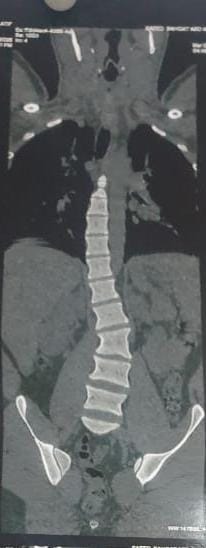

نجح فريق طبى بقسم جراحة المخ والأعصاب بمستشفى تمى الأمديد بالدقهلية فى إجراء اول جراحة دقيقة لإصلاح اعوجاج بالعمود الفقرى لشاب يبلغ من العمر 21 عاماً .

وأضاف مدكور أنه جرى استقبال المريض وهو يعانى من الالام شديدة بالظهر مع عدم الاستجابه للعلاج الدوائي والعلاج الطبيعى وعقب الفحص تبين وجود اعوجاج بالفقرات الصدريه والقطنيه بالعمود الفقري.

فيما أوضح الدكتور احمد البيلى وكيل المديرية للطب العلاجى أنه عقب مناظرة الاشعة والفحوصات تم إجراء العملية التى استغرقت 4 ساعات كاملة لإصلاح الاعوجاج بواسطه تثبيت الفقرات الصدريه والقطنيه واستعدال العمود الفقرى مع خروج المريض من المستشفى وتحسن حالته